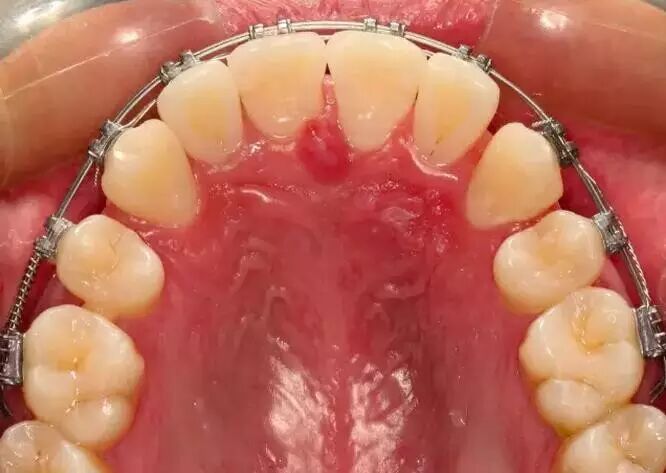

由于牙齿过于不整齐,患者拔除了四颗牙齿(上牙和下牙各拔两颗),然后通过戴牙套的方式,进行牙齿矫正,牙齿明显变的整齐:

这样的变化耗时15个月: